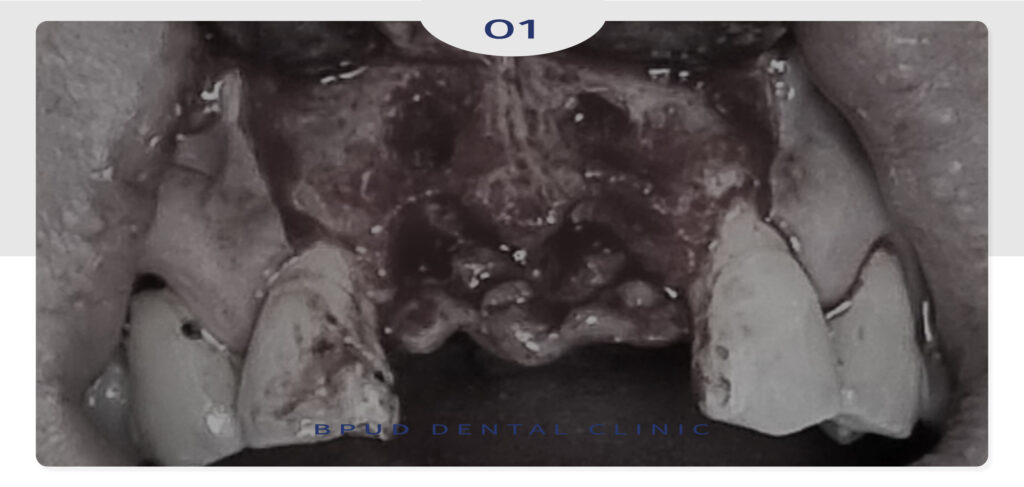

환자분께서는 심한 충치와 염증으로 인해

2주 전에 타원에서 위, 아래 앞니를 발치 후

지인 분의 소개로 부평유디에 내원해 주셨는데요.

이미 많은 양의 치조골이 흡수되신 상황으로

앞니 부위도 골흡수가 많이 진행되었으나

치조골 이식을 시행하여 볼륨을 회복할

수 있도록 하였는데요.